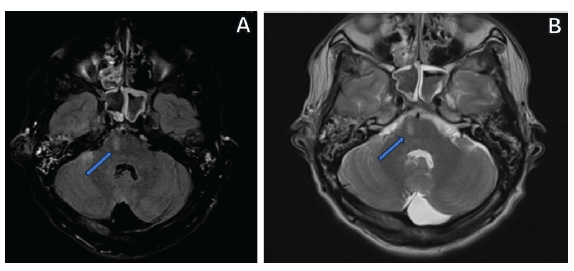

En consideración de los signos focales y con la sospecha de afectación del tallo cerebral, se indicó una resonancia simple de cráneo, donde como hallazgo se demostró una imagen hiperintensa en secuencia T2 y FLAIR, localizada en la zona ventral derecha de la protuberancia (figura 3), con lo cual se estableció el diagnóstico definitivo del síndrome de Millard-Gubler de origen traumático, por lo que se comenzó terapia antiinflamatoria con glucocorticoides endovenosos: metilprednisolona de 1000 mg cada día, por cinco días, y posteriormente, administración por vía oral de prednisona 60 de mg cada día, en dosis decreciente. Posterior al alta hospitalaria, se indicó fisioterapia motora y seguimiento por los servicios de Neurología y Oftalmología.

Resonancia magnética cerebral

Figura 3: Resonancia magnética cerebral

Nota: en la figura 3A se observa la resonancia en secuencia FLAIR y en la figura 3B se ve en secuencia T2, donde es visible la hiperintensidad en la región ventral derecha del puente (flecha azul).

Fuente: elaboración propia.